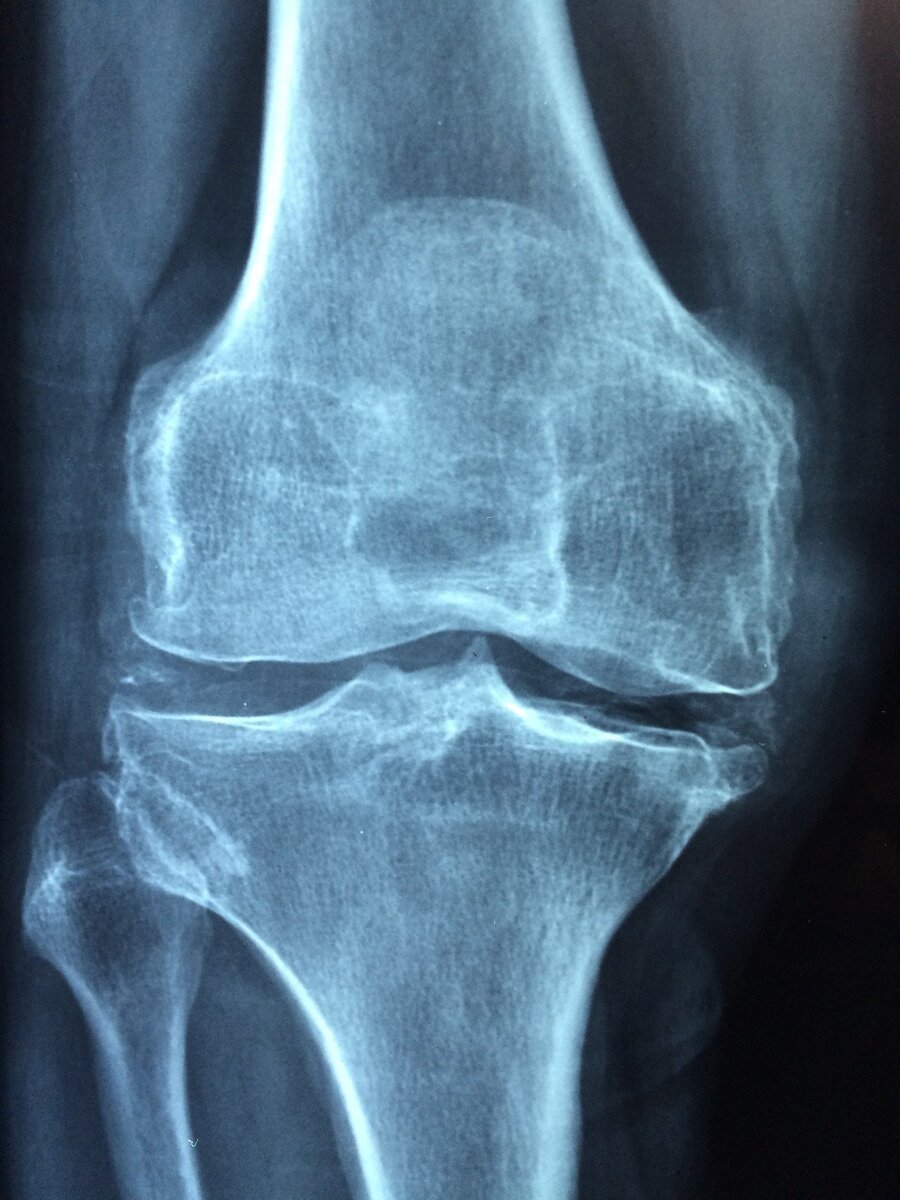

Заниматься спортом всегда хорошо, выглядеть подтянутым тоже замечательно. Сохраняйте свой вес в идеальном для вас состояния, без лишнего жира. Из-за избыточного веса нагрузка на наши суставы увеличивается в разы. Это может привести к повреждению и заблаговременному разрушению суставов. Избыточный вес в первую очередь разрушает колени.